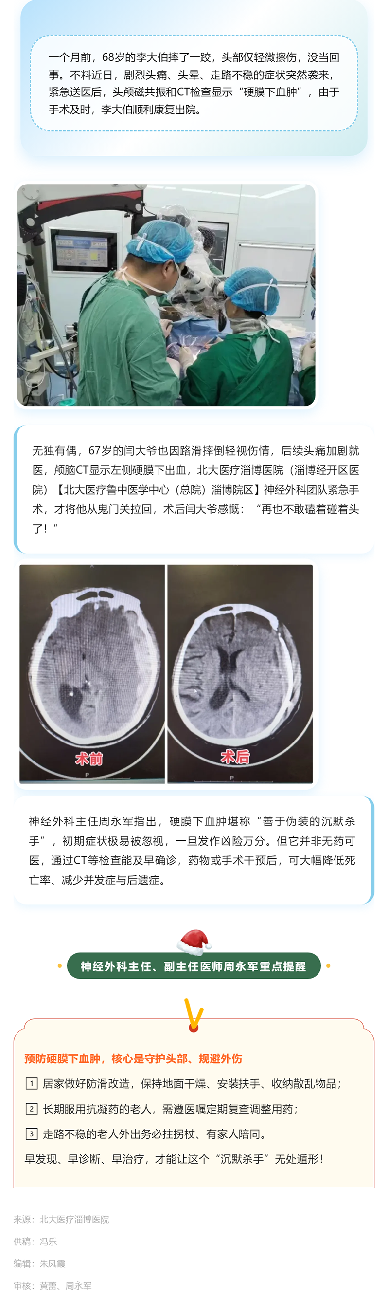

摔倒后沒事?可能只是假象!“硬膜下血腫”的延遲發(fā)作危機